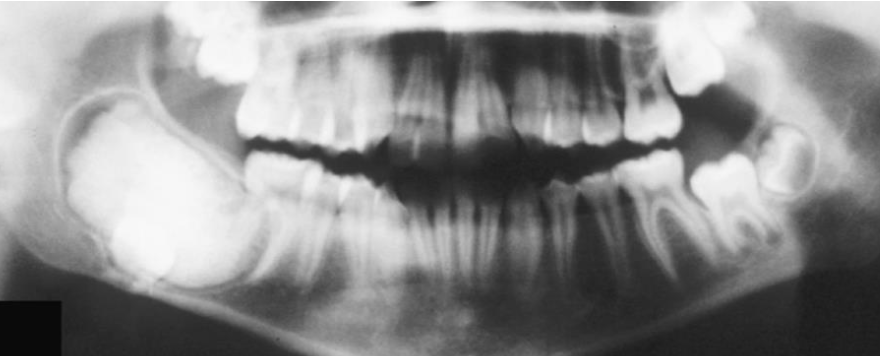

Odontoma compound 最常見 上顎前牙 20y ↓

• 構造順序排列

alt text alt text

complex 後牙

• dentin 和 enamel matrix 混在一起

• 有時可見嗜酸 Ghost cell